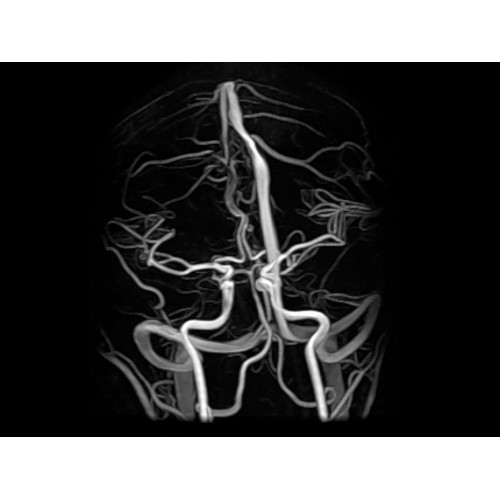

МР-ангиография Да

• Градиентная подсистема eXtreme — мощная градиентная подсистема для исследования тела характеризуется градиентом 34 мТл/м и скоростью нарастания градиента 150 Тл/м/с по каждой оси, что обусловливает быстроту, точность и высокую воспроизводимость сканирования.

• Цифровой РЧ-приемник OpTix — эксклюзивная оптическая РЧ-система увеличивает четкость сигнала и его интенсивность, формируя чистые и резкие изображения.